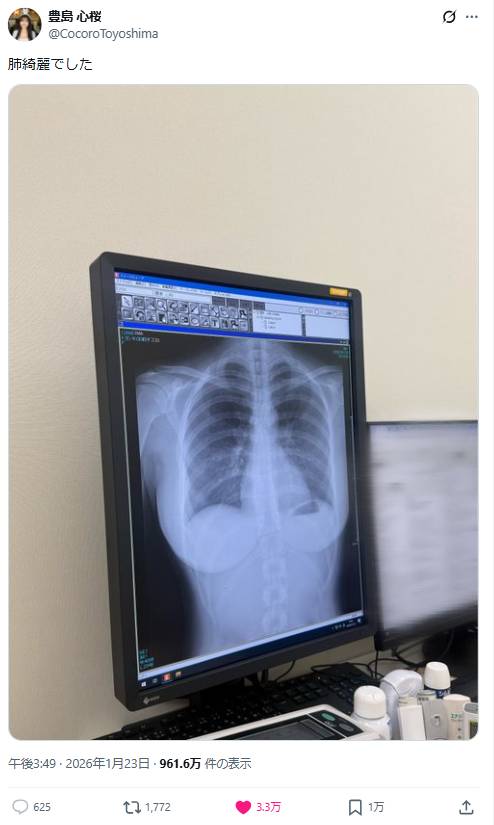

23歲日本最強body曬X光照「肺部健康」超邪惡線條狂吸3千萬瀏覽!

23歲日本寫真女神豐島心櫻近日因為一張健康檢查的X光照片意外爆紅,短短一天內吸引超過3,000萬人次瀏覽!她原本只是想向粉絲報告「肺很乾淨」的檢查結果,豈料網友目光完全沒有停留在肺部,反而被X光片中清楚呈現的身形線條吸引,相關截圖更在網上瘋傳!

豐島心櫻曬X光照報告健康狀況

豐島心櫻23日在社群平台X分享了自己的胸部X光照片,本意是向粉絲展示肺部檢查結果良好。這位擁有167公分身高、H罩杯傲人身材的新生代寫真偶像,配文簡單表示肺部狀況健康。照片上傳後迅速在社群平台上瘋傳,至今已累積超過3,880萬次觀看。

網友錯重點狂讚最強body!

網友的注意力幾乎完全沒有集中在肺部健康上,反而被X光影像中呈現出的胸形輪廓深深吸引。留言區迅速被各種充滿暗示性的評論佔據,不少網友直言「非常漂亮的肺」、「這形狀真不錯」、「這是我第一次看到這麼驚人的X光片」、「仔細看了一下,形狀真漂亮」。更有網友坦白表示「我看到的不是肺」、「順便說一句,妳的身材真好」。